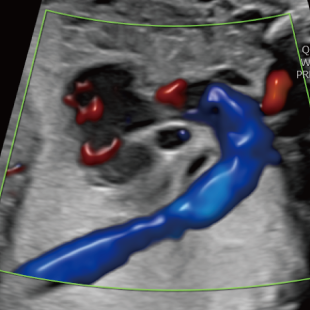

妊娠後期は、胎児の成長がさらに進み、発育の途中で現れてくる変化を確認できる時期です。中期の検査では問題が見られなかった場合でも、成長に伴って形態の変化が現れることがあります。また、構造だけではなく、胎児機能(赤ちゃんの元気度)の評価も可能となります。後期スクリーニングでは、各臓器の状態や構造に加え心臓の動きや血液の流れなどをより詳しく観察します。

胎児ドックの様子_後期_頭 胎児ドックの様子_後期_心臓 胎児ドックの様子_後期_心臓 胎児ドックの様子_後期_足 胎児ドックの様子_後期_4D